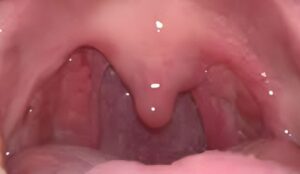

can tonsils grow back after being removed? – tymoff